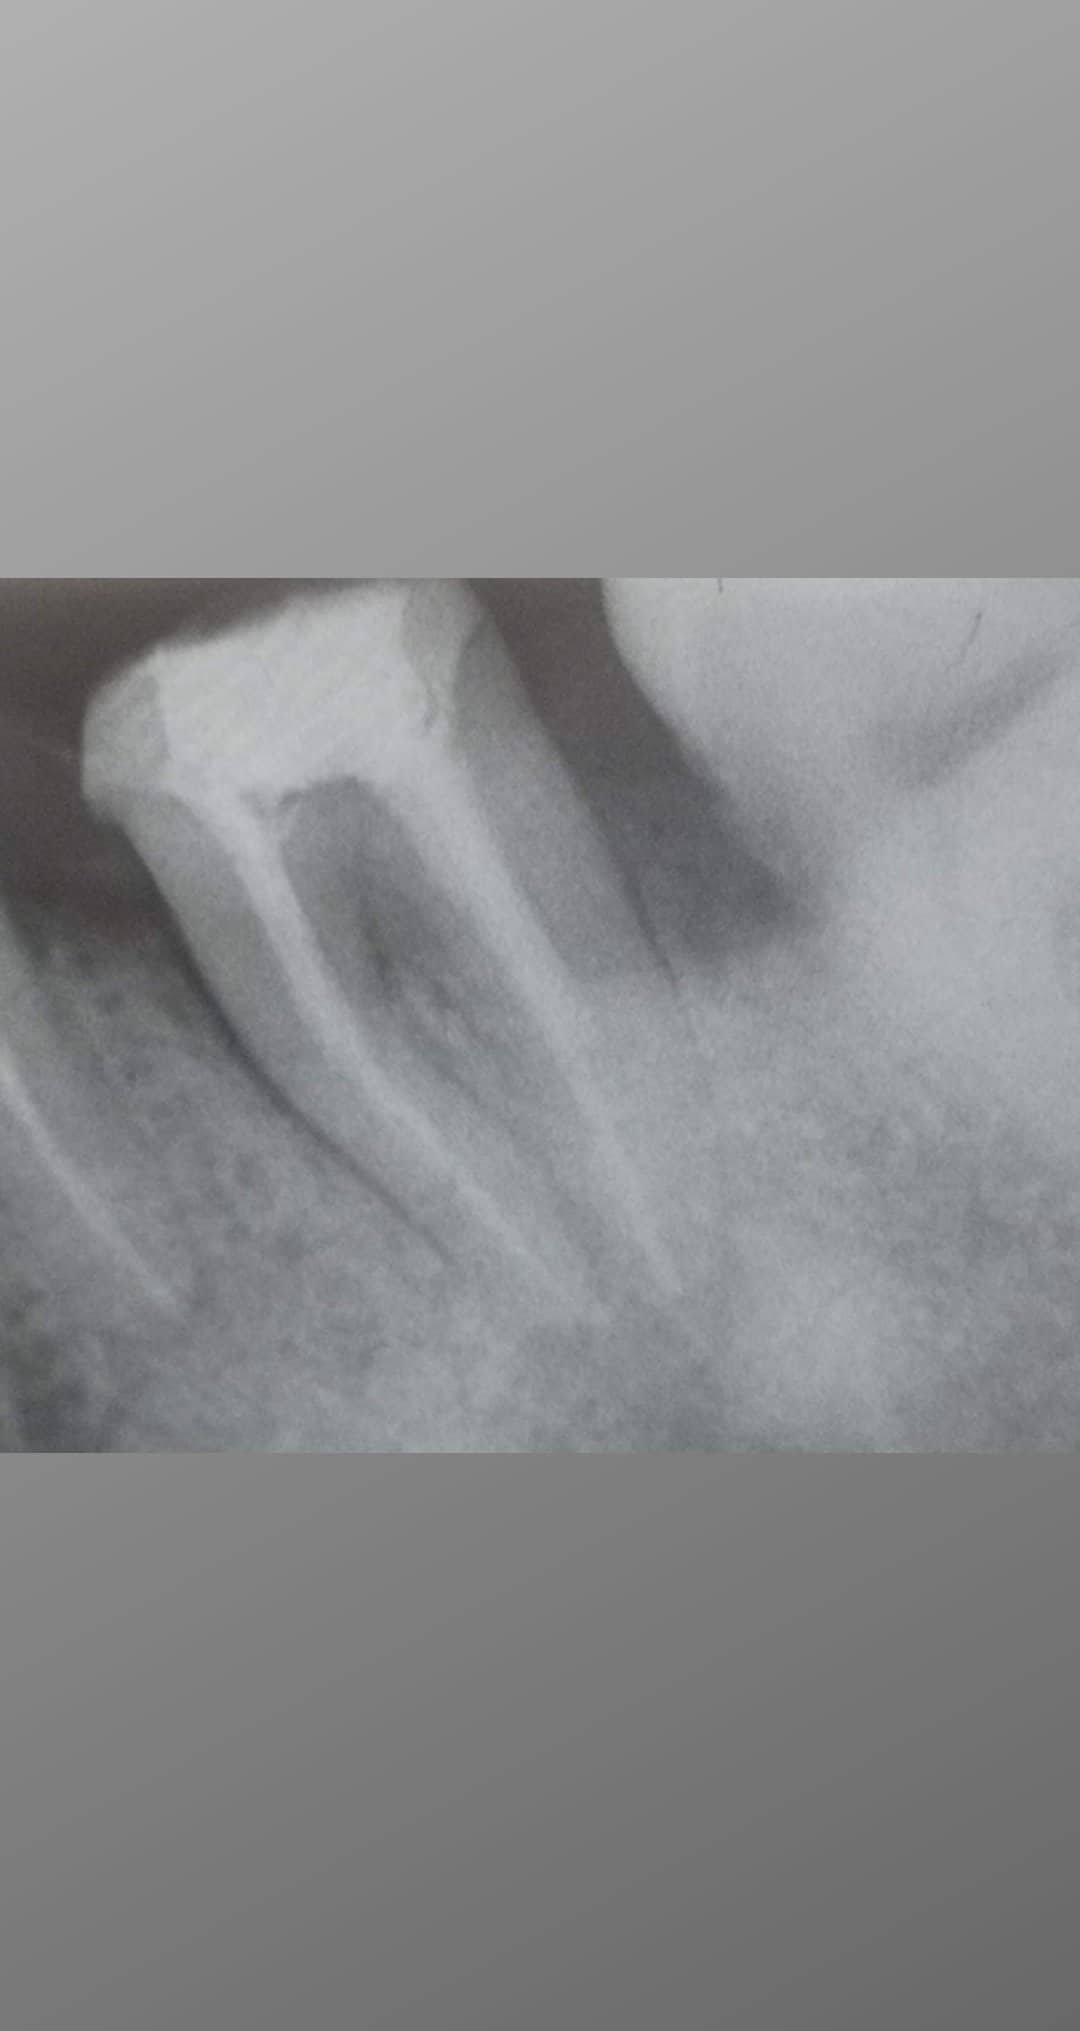

Авторе,сега ще чуеш мнението ,което ти е нужно .Ето какъв зъб може да бъде спасен

Хирургично се удължава зъба,как става това?Изрязва се венеца и костта и така вземаме от корена на зъба,за да може по този начин зъба да е над венеца

Слагаме кофердам,това е синьото платно,което се вижда тук.Ако зъболекарят не ползва кофердам,значи няма как да възстанови такъв зъб добре.

Запълват се каналите.

Слагат се фиброщифтове,за да може натоварването да се пренесе надолу към корена и да няма висок риск от счупване.

Накрая вземаме отпечатък и зъботехника прави корона.Завършен случай!Просто ти трябва добър зъболекар,а не средностатистически